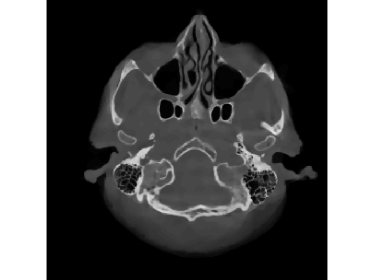

Finally, we apply the proposed method on a clinical head dataset. The data are acquired with a Siemens Artis zee angiographic C-arm system (Siemens Healthcare GmbH, Forchheim, Germany). In this experiment, we choose one slice of a 3D clinical head dataset as the ground truth image (Fig.9) and reproject it to simulate the acquired sinogram data in the fan-beam system with the following trajectory parameters: the source-to-isocenter distance is 750 mm and isocenter-to-detector distance is 450 mm. The angular step is 1 degree and the total scan range is 360 degrees. The equal-spaced detector length is 620 mm with the pixel length 111 mm.

The full projections are shown in Fig.10. When the detection range κ𝜅\kappa is limited, there could be saturation for the projection. In Fig.10 and Fig.10, observations for κ=0.6pmax𝜅0.6subscript𝑝\kappa=0.6p_{\max} and κ=0.4pmax𝜅0.4subscript𝑝\kappa=0.4p_{\max} are displayed, respectively. Our task is to recover the image from the saturated projections via M1bit-CS-ISD. The results are compared with FBP and SART, two standard CT reconduction frameworks. For FBP, we apply the modification given by [38] that utilizes water cylinder extrapolation to remedy missing projections caused by truncation or overexposure. For SART, one can remove those saturated projections when they are found, for which the ISD can be used as well. We denote this method as SART-ISD, of which the detection scheme is as the same as M1bit-CSR-ISD but SART is used as the reconstruction method.

For κ=0.6pmax𝜅0.6subscript𝑝\kappa=0.6p_{\max}, the reconstruction results of FBP-WCE and SART-ISD are given in Fig.9 and 9, respectively. As shown before, the traditional FBP method cannot handle the saturated data. With water cylinder extrapolation, the reconstruction quality has been improved but loss of clear patient boundaries still happens. The overall performance of SART-ISD is slightly better than FBP-WCE but capping artifact can be identified at the object border. Further improvement is obtained using the proposed M1Bit-CSR-ISD to acquire information from the saturated data. As shown in Fig.9, most of outer boundaries are nicely restored and streaking artifacts are effectively eliminated.

Next, we artificially add Gaussian noise on the projections and the standard deviation of the noise σ=0.1𝜎0.1\sigma=0.1. The reconstructed images of FBP-WCE (with a smooth filter), SART-ISD, and M1bit-CSR-ISD are displayed in Fig.11. Comparing the images in Fig.9 and 11, we can find that the proposed method is not sensitive to additive noise, which is rooted in the loss functions of (5) and (6). If the projections contain outliers, then some robust losses can be applied.